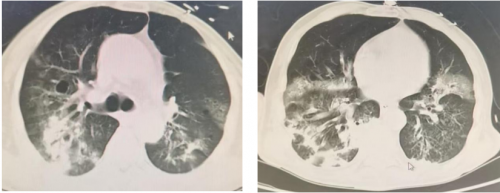

2025-10-28复查胸部CT:气管插管术后,气管腔内可见高密度影附着。桶状胸廓,双肺可见多发类圆形无壁及薄壁透光区,双肺内可见散在斑片状稍高密度影,边缘模糊不清,部分实变。双侧胸腔内可见弧形液体密度影,右侧为著。主动脉及冠状动脉走行区可见致密影。双侧胸腔内未见积液。